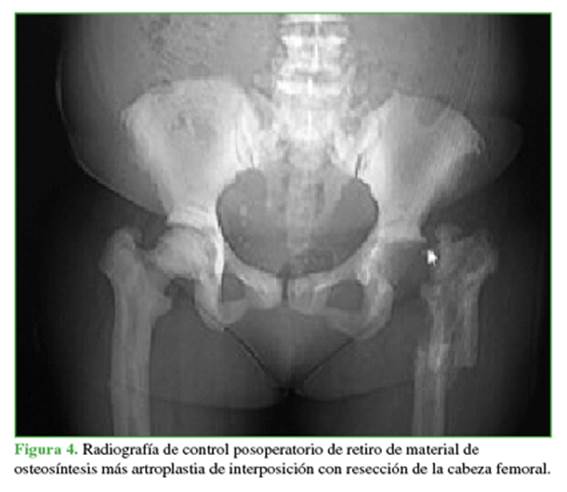

Durante la evolución posoperatoria por la presencia de pseudoartrosis (diagnosticada a los 6 meses de la operación y manejada en otra institución), se realiza retiro de material de osteosíntesis (clavo intramedular bloqueado) y resección de la cabeza femoral, por lo que queda en artroplastia de resección (Figuras 3 y 4).